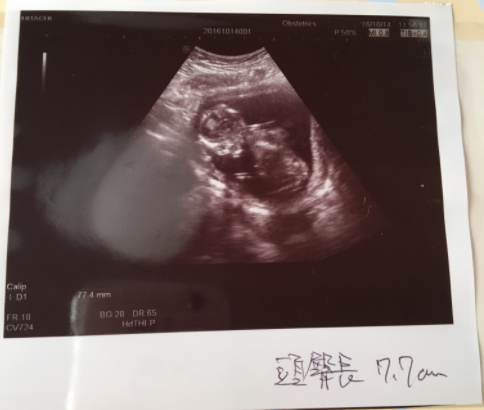

16週6日(16w6d・男の子)|keiichi さん(32歳)

エコー写真撮影時のエピソード:

待ちに待った安定期。前回の診察から間があいたのでドキドキしながらエコーに臨んだら、背骨がくっきり見えました!たまたま母と一緒に診察に行った日で、初孫のエコーに母がはしゃいでいたのを良く覚えています。帰ってから写真を見せたら、パパも大喜びしていました。